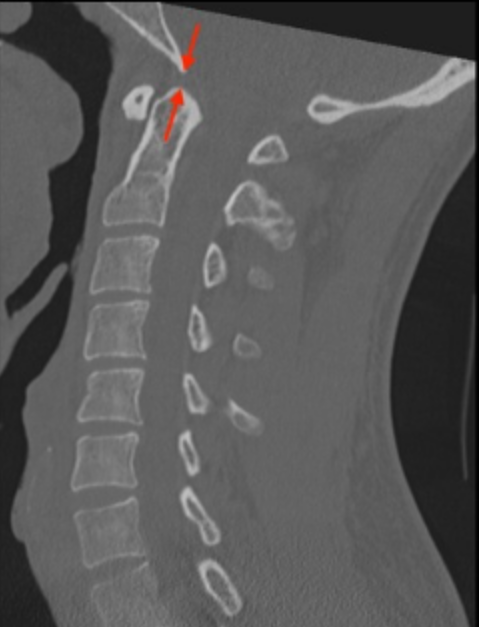

BDI evaluates vertical alignment between the skull base and the upper cervical spine. It is primarily used to detect vertical distraction injuries and atlanto-occipital dissociation.

• Use a midsagittal CT image.

• Identify the basion (anterior margin of the foramen magnum). Locate the lowest, most posterior point of the clivus in the midline.

• Locate the most superior tip of the odontoid process.

• Measure the distance from the basion to the tip of the dens.

• CT Normal Values: Studies by Rojas et al. and others have defined the normal BDI on CT as <8.5-<10 mm. A BDI > 10 mm on CT is highly suspicious for AOD.